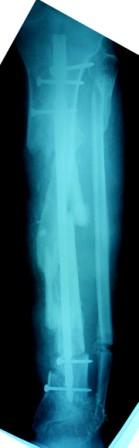

3) Третьим этапом наложили модуль на промежуточный фрагмент.(рис 3)  И начали его транспорт на стержне в проксимальном направлении. (рис 3 а)

Имя     : Рис 3 Рентг до Начало транспорта фрагмента 6.03.09.JPG

Тип     : image/jpeg

Размер  : 17610 байтов

Описание: отсутствует

Url     : http://weborto.net:8080/pipermail/ortho/attachments/20090405/a3dc024e/attachment-0015.jpeg

Имя     : Рис 3 Рентг до Начало транспорта фрагмента 6.03.09 (1).JPG

Размер  : 17307 байтов

Url     : http://weborto.net:8080/pipermail/ortho/attachments/20090405/a3dc024e/attachment-0016.jpeg